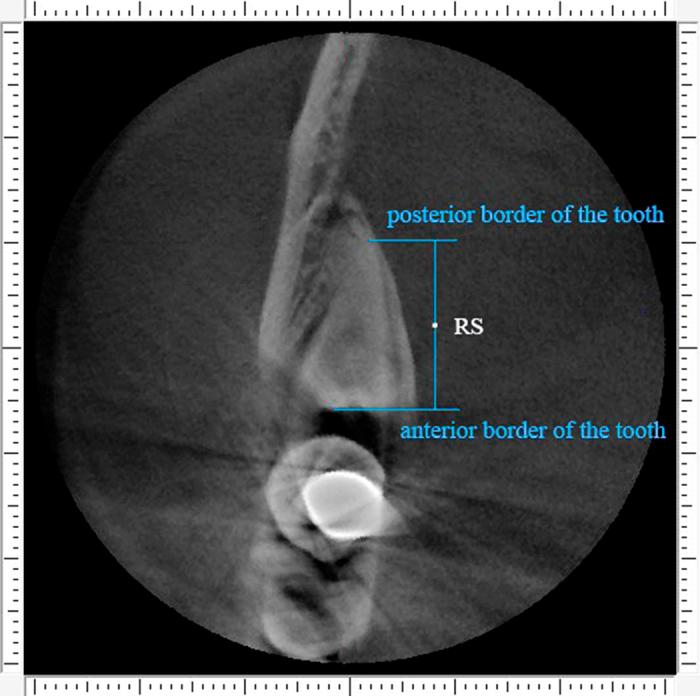

Selecting either buccal or lingual approach for the mandibular third molar surgical extraction has been an intense debate for years. The aim of this observational retrospective study was to classify the molar based on the proximity to the external cortical bone, and analyze the position of inferior alveolar canal (IAC) of each type. Cone-beam CT (CBCT) data of 110 deeply impacted mandibular third molars from 91 consecutive patients were analyzed. A new classification based on the mean deduction value (MD) of buccal-lingual alveolar bone thickness was proposed: MD≥1 mm was classified as buccal position, 1 mm>MD>-1 mm was classified as central position, MD≤-1 mm was classified as lingual position. The study samples were distributed as: buccal position (1.8%) in 2 subjects, central position (10.9%) in 12 and lingual position (87.3%) in 96. Ninety-six molars (87.3%) contacted the IAC. The buccal and inferior IAC course were the most common types in impacted third molar, especially in lingually positioned ones. Our study suggested that amongst deeply impacted mandibular third molars, lingual position occupies the largest proportion, followed by the central, and then the buccal type.

多年来,对于下颌第三磨牙手术拔除选择颊侧或舌侧入路一直存在激烈争论。这项观察性回顾性研究的目的是根据下颌第三磨牙与外侧皮质骨的接近程度对其进行分类,并分析每种类型下颌管(IAC)的位置。分析了91例连续患者的110颗深度埋伏下颌第三磨牙的锥形束CT(CBCT)数据。提出了一种基于颊舌侧牙槽骨厚度平均差值(MD)的新分类方法:MD≥1mm分类为颊侧位置,1mm>MD>-1mm分类为中央位置,MD≤-1mm分类为舌侧位置。研究样本分布如下:2例患者的颊侧位置(1.8%),12例患者的中央位置(10.9%),96例患者的舌侧位置(87.3%)。96颗磨牙(87.3%)与下颌管接触。颊侧和下颌管在下颌管走行是埋伏第三磨牙中最常见的类型,尤其是舌侧位置的。我们的研究表明,在深度埋伏下颌第三磨牙中,舌侧位置占比最大,其次是中央位置,然后是颊侧类型。